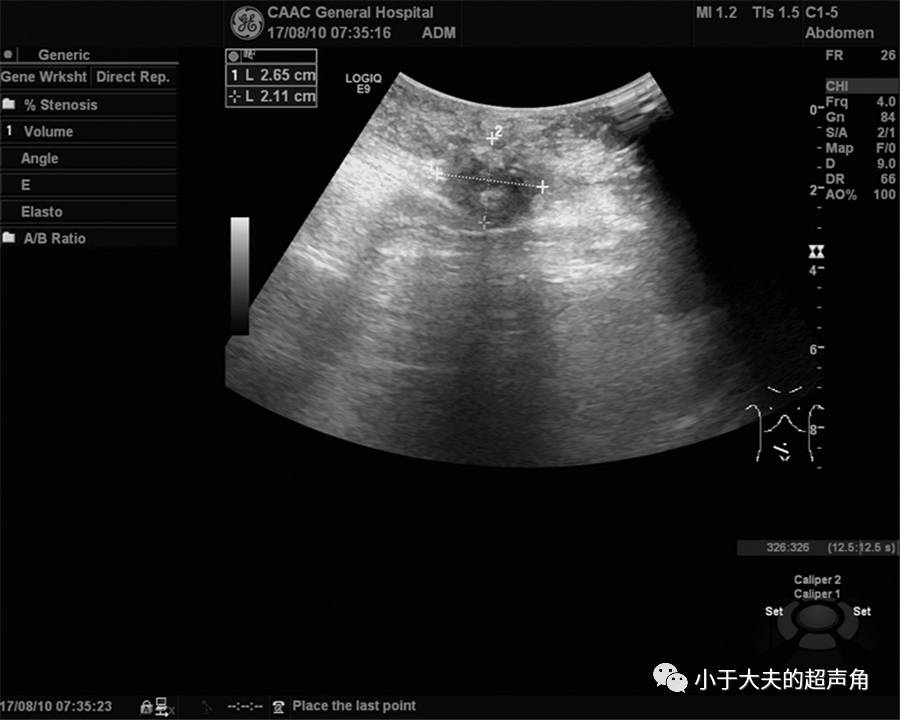

上图:果然,在紧邻肠管的既往手术切口处肌层内,发现不规则偏低回声,大小约4.2×3.0cm,边界模糊不清。

上图:CDFI:偏低回声内未见明显血流信号。

上图:既往切口深方另一处占位,边界模糊不清,内部回声减低不均。

上图:CDFI:内部也未探及明显血流信号。